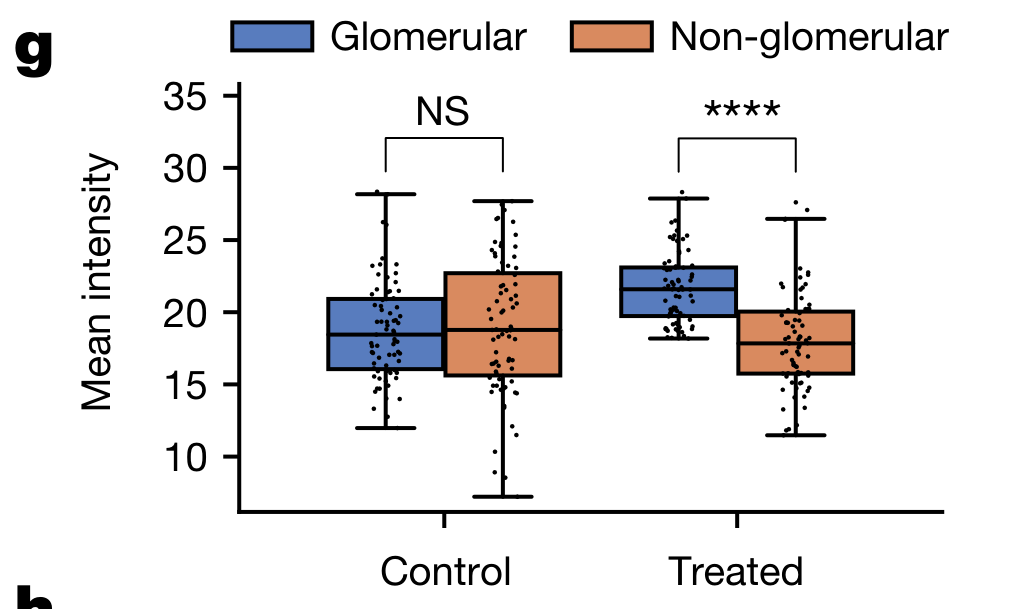

Li X. et al. - 2025

SPEX: A modular end-to-end platform for high-plex tissue spatial omics analysis

Condition Dimension

N/A

Data Components

Gene Expression Matrix

Data

Metadata

None

Modality

Proteomics

Resolution of observation

Cellular

Visualized Elements

FeatureObservation

Biological

Molecular

Abstraction

CompleteNone

Chart Type

Dimensionality reductionScatterplotSpatial Gene Expression Map

Communicative/Contextualization

Annotation

Comparative Design

JuxtapositionJuxtaposition : Small multiples

Layout

Spatial : LatentSpatial : Physical

Scalability Strategy

Sampling/Filtering

Where are specific proteins expressed in both expression space and physical tissue space?